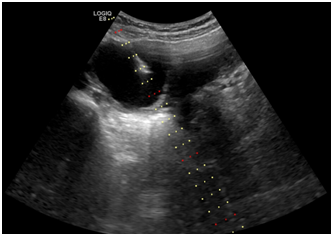

德州市第二人民医院超声医学科主任医师石洪柱接诊后为其进行了术前查体、定位,在超声引导下穿刺囊肿,抽出暗红色囊液,用生理盐水冲洗囊腔,聚桂醇硬化囊腔。做完第一个囊肿后,穿刺针不拨出体外,连续穿刺了第二个、第三个囊肿。每个囊肿在硬化后均保留3-5ml聚桂醇。整场操作娴熟流畅、全程无痛,治疗三个囊肿只在肚子上看到一个小针眼。术后,病理结果支持子宫内膜异位囊肿,让小丽感觉到前所未有的轻松。术后2个月复查,小丽患侧卵巢恢复正常,囊肿完全消失,疗效评价为治愈。